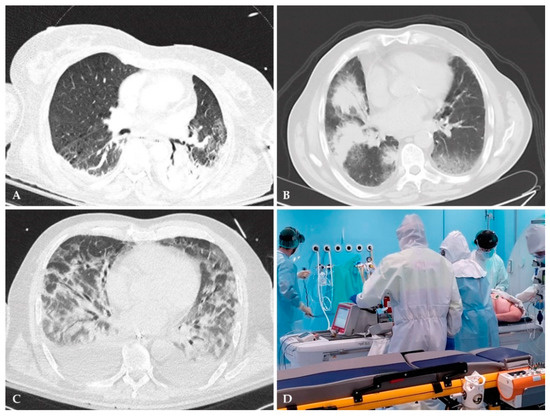

- Hoesein, F.M. Low-dose computed tomography instead of radiography in suspected pneumonia. Breathe 2019, 15, 81–83. [Google Scholar] [CrossRef]

- Prendki, V.; Scheffler, M.; Huttner, B.; Garin, N.; Herrmann, F.; Janssens, J.-P.; Marti, C.; Carballo, S.; Roux, X.; Serratrice, C. Low-dose computed tomography for the diagnosis of pneumonia in elderly patients: A prospective, interventional cohort study. Eur. Respir. J. 2018, 51, 1702375. [Google Scholar] [CrossRef]

- Kroft, L.J.; van der Velden, L.; Girón, I.H.; Roelofs, J.J.; de Roos, A.; Geleijns, J. Added value of ultra-low-dose computed tomography, dose Equivalent to chest x-ray radiography, for diagnosing chest pathology. J. Thorac. Imaging 2019, 34, 179. [Google Scholar] [CrossRef] [PubMed]